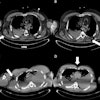

Team Sicily shines light on imaging of gunshot wounds